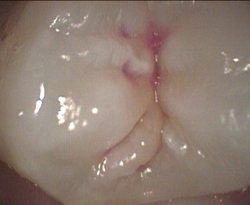

Unusual prevalent but superficial groove pattern on permenant molar after Sealed